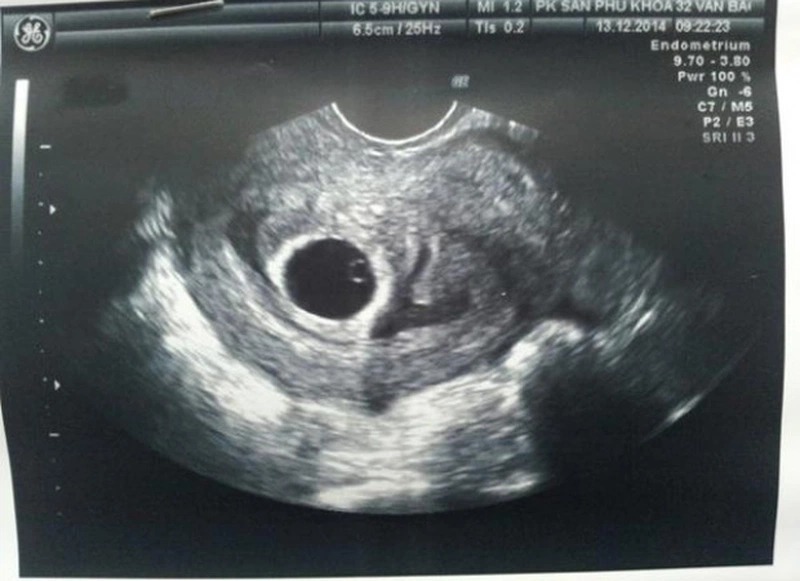

Hiện tượng xuất hiện yolksac trong siêu âm thai là dấu hiệu sớm cho thấy phôi thai đang phát triển bình thường trong tử cung. Yolksac thường được nhìn thấy ở tuần thai thứ 5 – 6 thông qua siêu âm đầu dò, xuất hiện dưới dạng một vòng tròn nhỏ, sáng bên trong túi thai. Sự có mặt của yolksac chứng tỏ quá trình thụ tinh và làm tổ đã thành công, là bước quan trọng trước khi quan sát thấy tim thai. Nếu sau tuần thứ 6 túi thai không xuất hiện yolksac, bác sĩ có thể nghi ngờ thai ngoài tử cung hoặc thai lưu.

Yolksac trong siêu âm thai hoàn toàn không nguy hiểm mà ngược lại còn là dấu hiệu tích cực cho thấy thai đang phát triển bình thường. Đây là cấu trúc tự nhiên và cần thiết trong giai đoạn đầu của thai kỳ, giúp nuôi dưỡng phôi khi nhau thai chưa hoàn thiện. Tuy nhiên, nếu yolksac có hình dạng méo mó, quá to hoặc quá nhỏ (thường >6 mm hoặc <2 mm) có thể là dấu hiệu cảnh báo bất thường trong quá trình phát triển của thai nhi. Khi bác sĩ phát hiện yolksac bất thường, thường sẽ chỉ định theo dõi sát và kiểm tra lại bằng siêu âm ở các tuần tiếp theo.